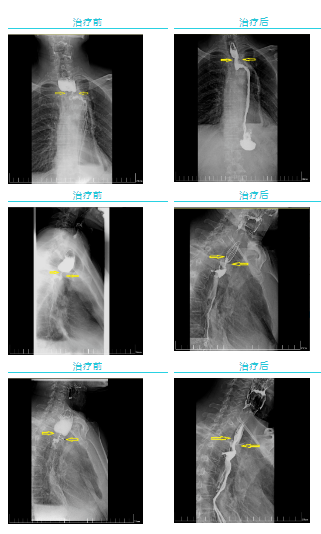

經過一個周期的放療,李先生明顯感受好多了,可以正常吃飯喝水。食管鋇餐造影顯示,食管吻合口區(qū)腫塊明顯縮小,食管狹窄減輕。